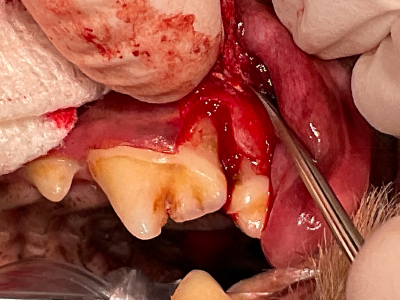

オープンフラップデブライドメント

オープンフラップデブライドメント開始。歯肉を切開してみると、あるべき骨はなく根っこが露出していて歯石まみれになっています。

オープンフラップデブライドメント完了

マイクロスコープを用いて根っこの表面を徹底的に清掃します。